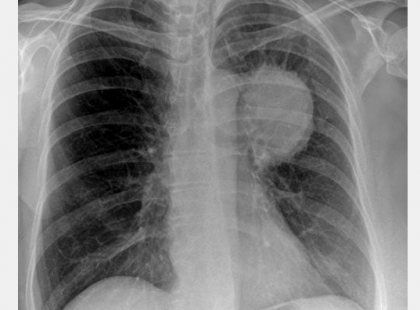

Édesanyám egy hónap alatt gyógyult ki a tüdőrákból ezzel a módszerrel. Naponta három kiskanállal ebből a keverékből:

Édesanyám pépesített spárgát és minden reggel 4 evőkanállal evett meg reggelire belőle. Majd ezt tette minden egyes nap...